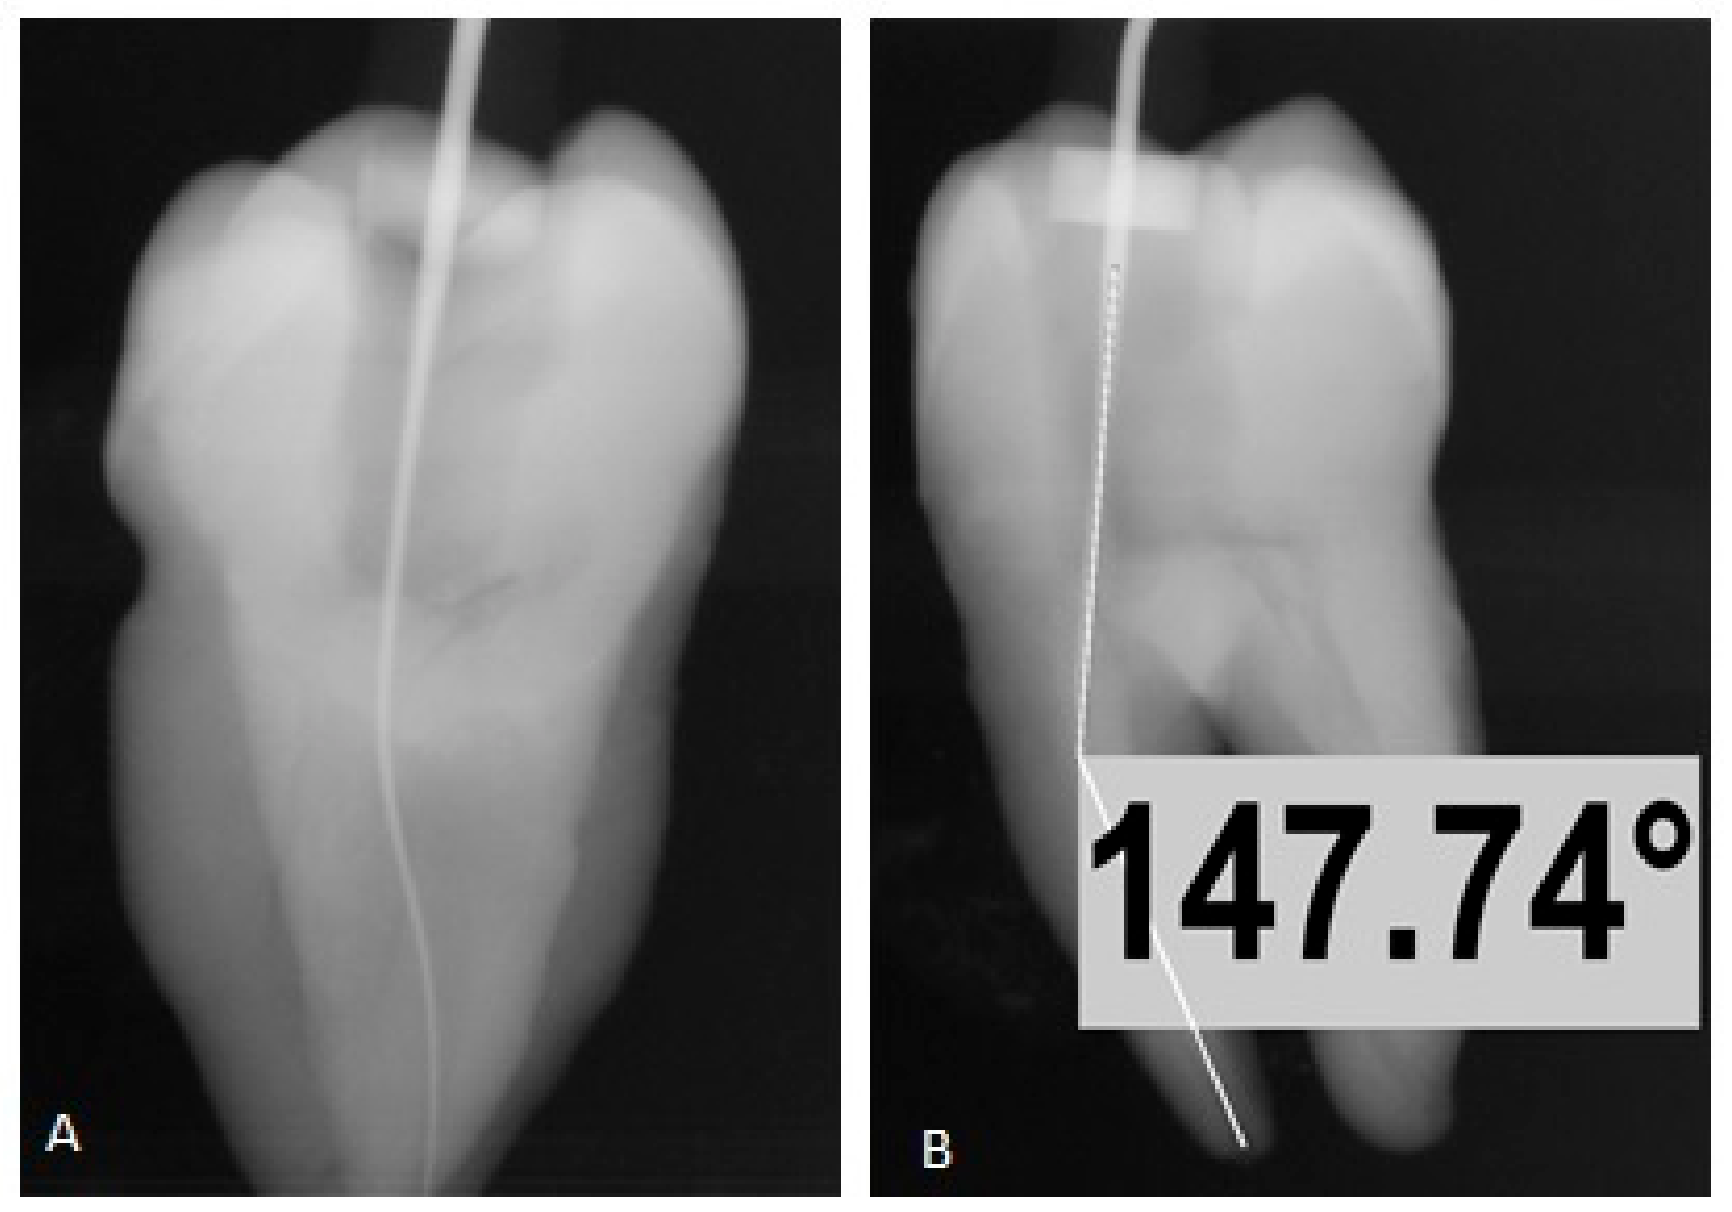

From www.researchgate.net

Techniques to measure the angulation of root canals. a. Schnieder(S),... Download Scientific How To Measure Root Canal Length  Diagnostic length radiographs, electronic apex locators, and the consistent drying point, 1 and during.   electronic root canal length measuring devices (erclmds) offer a means of locating the most appropriate endpoint. The determination of accurate working length is one of the most critical step in the endodontic therapy. Clt=kli x alt / ali.  there are three methods for determining. How To Measure Root Canal Length.